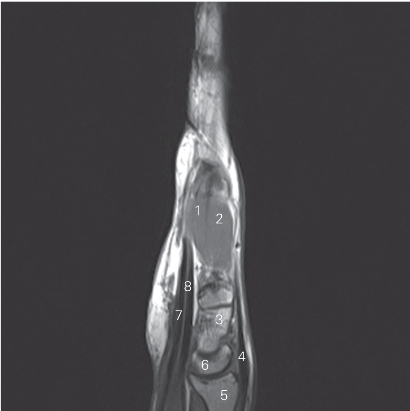

图4-49 经舟骨外侧份的矢状断层MR T1加权图像

1 骨间掌侧肌 palmar interossei 2 骨间背侧肌 dorsal interossei

3 头状骨 capitate bone 4 伸肌腱 tendon of extensor

5 桡骨 radius 6 月骨 lunate bone

7 指浅屈肌腱 tendon of flexor digitorum superficialis

8 指深屈肌腱 tendon of flexor digitorum profundus